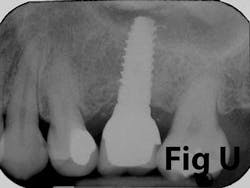

Case No. 1